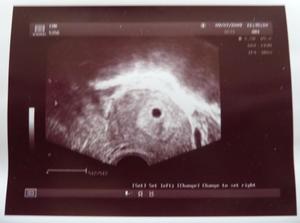

2.7.2009: jsem byla na 1. UZ v CAR - výsledek = prý je vidět jen (nebo zatím)jeden bobísek.Mám svou 1.fotečku!!! Byla odebrána krev na hCG = 392 (MUDr říkala,že ho typuje k tomuto dni kolem 700)Tak nevím,zda to není málo?! Předepsán dále Crinone.Další UZ 9.7.2009

7.7.2009 - opět kontrolní odběr na hCG.Výsledek : kooonečně hodnota poviskočila na 2111

9.7.2009 : 2.UZ : Je vidět gestační váček.K dnešnímu dni jsem 6+2 ale dle MUDr.Jarošové to ale záhadně vypadá spíše o týden měně(neumí si to vysvětlit) tudíš 5+2.Opět to nemůže být bez zádrhelu?! Jinak vše v pořádku.Kontrola raději 16.7.2009